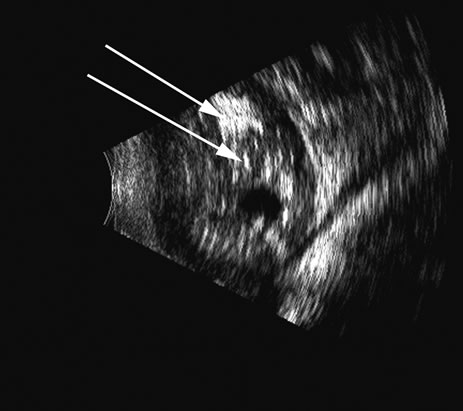

Hypotony is easily diagnosed by direct measurement of intraocular pressure, but the underlying cause is difficult to evaluate.11 High-frequency ultrasound scans can easily reveal separation of the ciliary body and the sclera. This allows different forms of hypotony to be determined—for example: tractional with membrane attached; primary as idiopathic, often inflammatory or hemorrhagic; and dehiscence secondary to iridodialysis or scleral perforation (Fig. 6). |